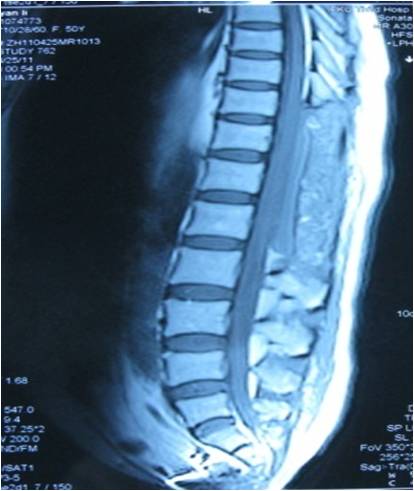

获奖病例展示---罕见全椎管脊髓囊虫病诊治